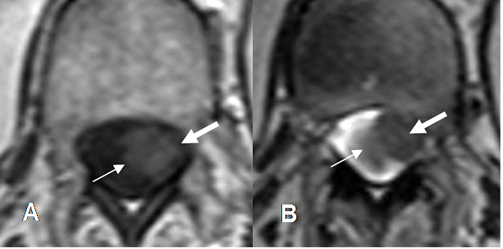

Fig 234. Lesión intradural extramedular.

A: RM axial en T1 y B: RM axial en T2. Imagen isointensa en T1 e hipointensa en T2, que ocupa la región paramediana izquierda.

Fig 235. Lesión intradural extramedular.

A: RM sagital en T2, B: RM sagital en T1 simple y C: RM sagital en T1 con contraste. Igual paciente anterior. Lesión ovalada y de bordes bien definidos, que comprime la medula espinal y realza con el contraste. En C se aprecia cola dural (Flecha gruesa), por meningioma intradural extramedular.